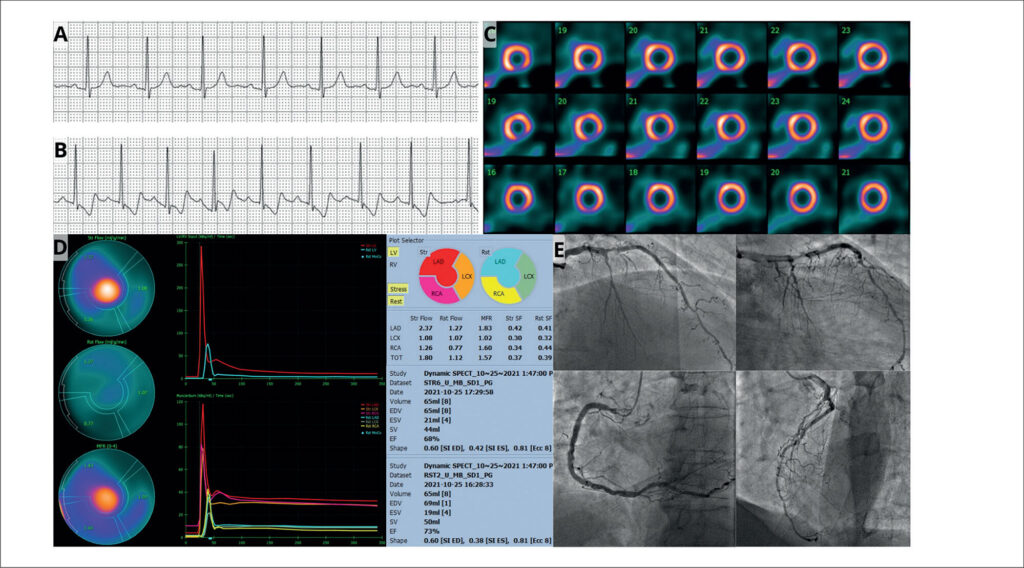

This case report presents a myocardial perfusion analysis in a 67-year-old asymptomatic male patient with known coronary artery disease (CAD) and multiple risk factors. While myocardial perfusion Imaging (MPI) with single-photon emission computed tomography (SPECT) revealed a 5% area of ischemia, the myocardial blood flow quantification assessment in a camera equipped with cadmium-zinc-telluride (CZT) detectors demonstrated a reduced global myocardial flow reserve (MFR) of 1.57. Coronary angiography confirmed extensive multivessel disease, including an 80% stenosis in the left anterior descending artery (LAD) and an occlusion of the circumflex artery (LCx), findings not fully identified by the semi-quantitative SPECT MPI. This case underscores the importance of MFR assessment, particularly using CZT technology, in detecting significant CAD that may be underestimated by traditional SPECT methods. It highlights the potential of dynamic CZT SPECT to provide more comprehensive functional information, enhancing risk stratification and potentially influencing patient management in complex cases of suspected or known CAD.